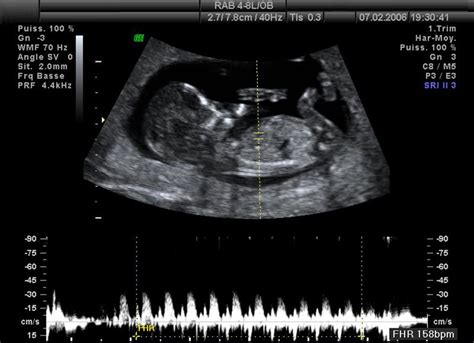

12. týždeň tehotenstva (3. mesiac): Dieťatko sa v maternici začína hýbať, ale pohyby ešte necítite, na ultrazvuku ste však už určite bola svedkom jeho akrobatických kúskov a trhaných pohybov telom aj končatinami.